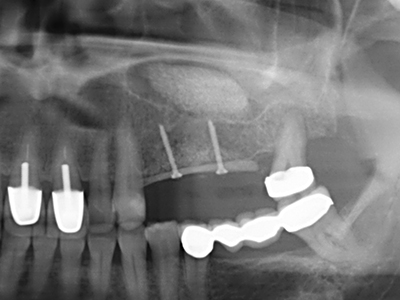

As shown in the past, basically any bone surgery procedure represents a possible indication for piezo surgery. Thus preparation of the mobile segment in distraction osteogenesis (Fig. 23-25) and sandwich osteotomy uses special attachments without endangering the blood supply to the crestal section, which is essential for the success of both techniques (Gonzalez-Garcia, Diniz-Freitas et al. 2008).

Purely orthodontic indications include orthognathic surgery, genioplasty (Fig. 27-30) and orbital decompression in patients with advanced endocrine orbitopathy as a result of Basedow’s disease (Ponto, Zwiener et al. 2014). Piezo devices are also used in maxillofacial surgery and to remove tumours at the base of the skull in various hospitals.